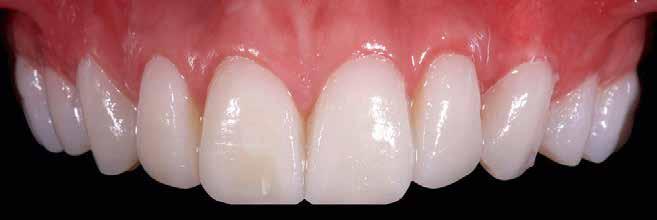

A fogak extrahálása és az alveoláris plasztika teljes narkózis mellett történt meg, így teremtve ideális helyzetet a protetikai ellátáshoz. A műtéti beavatkozás után a páciens az ideglenes fogsorral távozott. Egy héttel később jött kontrollra. Nemcsak látványra változott meg nagymértékben, hanem egyértelműen magabiztosabb és önbizalommal teli volt a fellépése (12. ábra)

Az elsődleges terápiás szakasz kulcsfontosságú volt a teljes rehabilitáció szempontjából. A páciensnek nem csak szép, esztétikus mosolyt kölcsönzött, hanem életminőségének javulását is hozta (13. ábra). A Digital Denture folyamatnak köszönhetően a kezelés ráfordításai is alacsonyak voltak. A fiatal nő messzemenően boldog, magabiztos és motivált a következő lépéshez.

12. ábra: Páciensünk egy héttel fogainak extrahálása és az ideglenes fogsor azonnali behelyezése után. 13. a–d ábrák: Látványos átalakulás: kezelés előtt és után. A páciens maga hangsúlyozta ki életminőségének jelentős javulását.